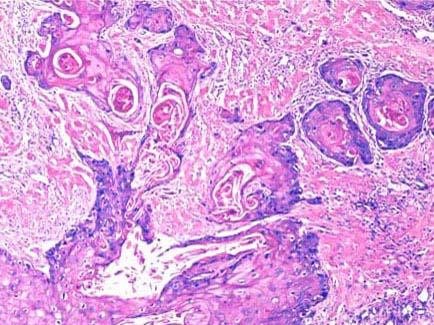

问题 患者,男,56岁,进行性声嘶2周,喉镜见声门区见一菜花状肿物,约2cm×1cm×0.6cm大小,取活检镜下如图所示,该患者正确的诊断是 ( )

选项 A.声带息肉 B.喉结核 C.慢性咽喉炎 D.喉鳞状细胞癌 E.喉乳头状瘤

答案 D